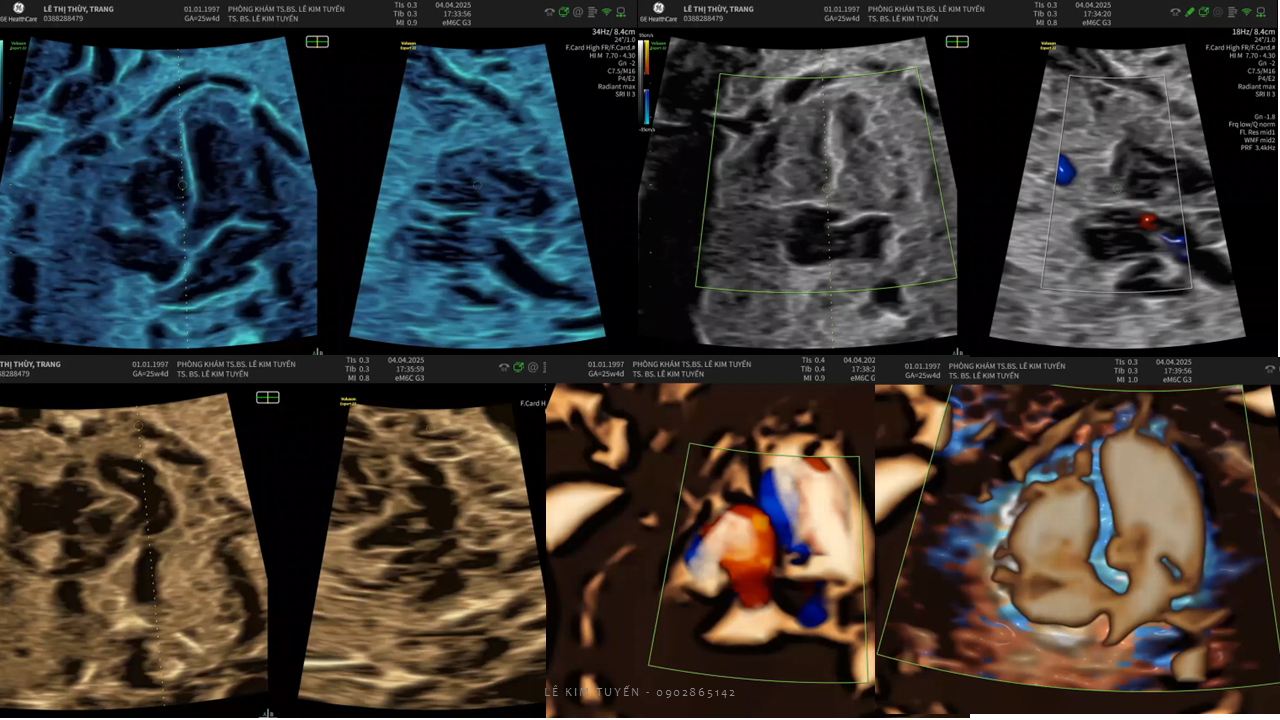

Siêu âm tim thai - Các kỹ thuật hiện đại

TS. BS. Lê Kim Tuyến

Bệnh viện Tim Tâm Đức